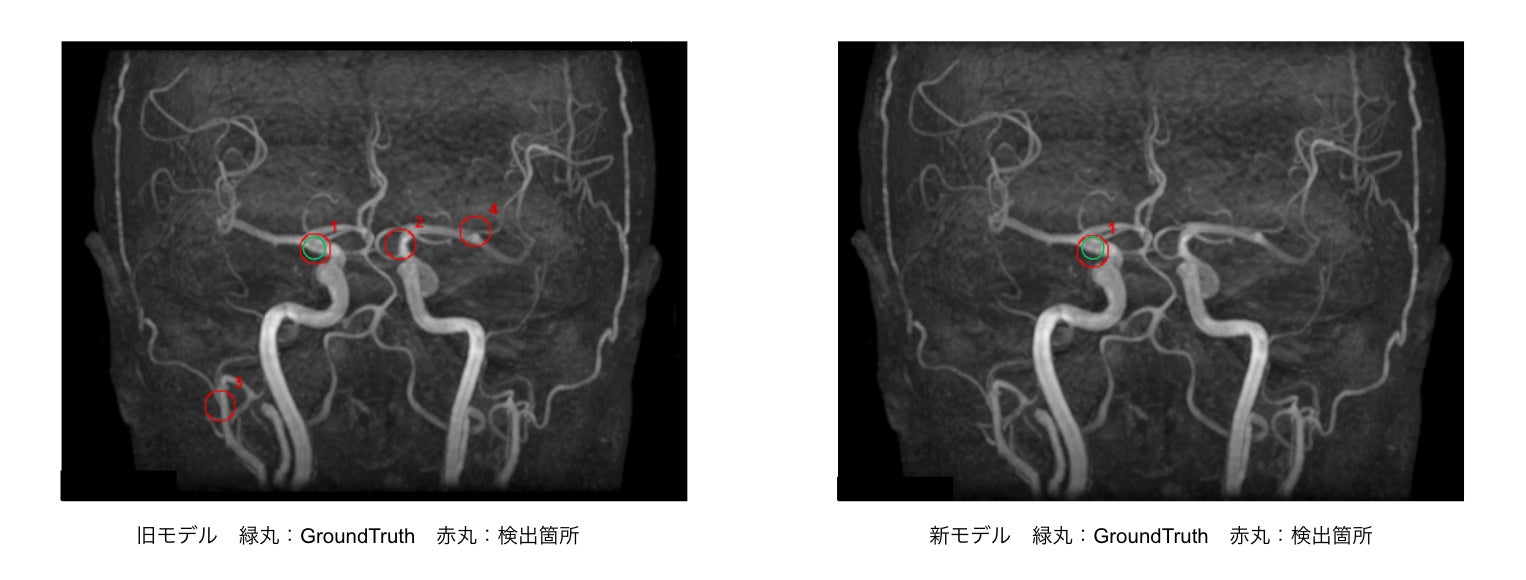

・旧モデルと比較して「偽陽性」が低減した症例

・脳底動脈の検出事例

※いずれの検出例もイメージであり、実際の製品表示とは異なる場合があります。

EIRL Brain Aneurysでは、脳動脈瘤の候補点について1症例あたり最大4つを検出し、表示します。今回、一部変更申請を取得した新バージョンでは感度92.3%、1症例あたりの偽陽性の検出数が「1」以下となりました。

新モデルでは、学習データの追加学習に加えてアルゴリズムの見直しを行うことで、検出感度を維持しながら、症例あたりの平均偽陽性数を「1」以下となるよう改善を行いました。